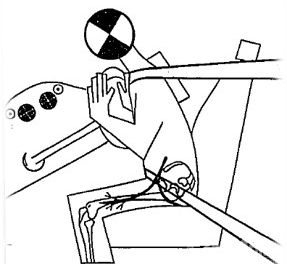

安全带导致LFCN损伤

感觉异常性股痛的病因来源只要与股外侧皮神经的损伤有关都会发生,局部神经的病变,神经走行区周围组织的病变等等,例如L2、3神经根的压迫、L2腰椎周围的肿瘤、腹膜后肿物压迫、髋关节活动过度、不良姿势、持续的局部肌肉痉挛、紧身的背带或束腰、大腿的外伤等等。